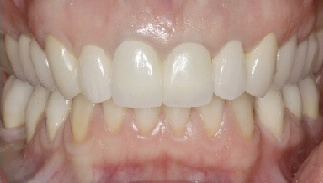

Probleem. Vanad, ebaesteetilised metallkeraamilised kroonid, kulunud hambad, sügav hammustus.

Lahendus. Hambaproteesidele paigaldatakse tsirkooniumoksiidist keraamilised kroonid ja hammustuskõrgust tõstetakse.